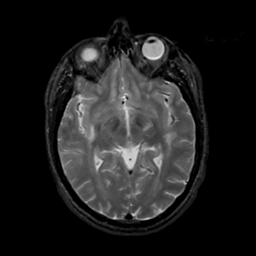

MR Study #4, March 3, 1991 -- Slice #23

[Home][Help][Clinical][Tour 1][Tour 2] Slice 23